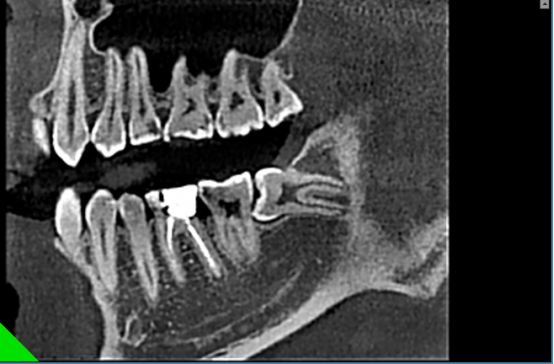

正畸通过扫描形成图像,包括曲面体层、头颅侧位进行测量图像。2D和3D图像在确定多生牙的存在及位置方面,有着巨大的差别。3D图像对扫描区域有着完整,综合的展示,甚至允许通过不同视角,以及对不同断面重建图像进行观察。